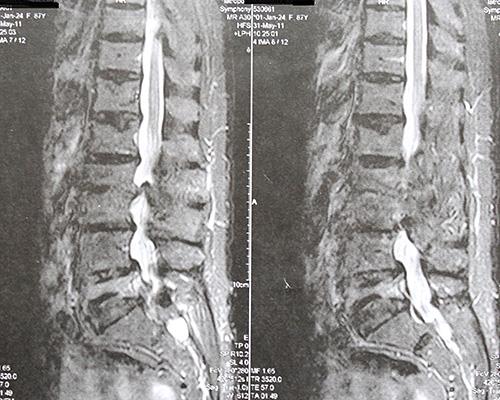

Πλήρης ακινησία, χειρουργικές επεμβάσεις και ακτινογραφίες με τη σέσουλα, ασθενείς με ταμπέλες αναπηρίας. Μήπως πρέπει να αναθεωρήσουμε την αντιμετώπιση των μυοσκελετικών πόνων;